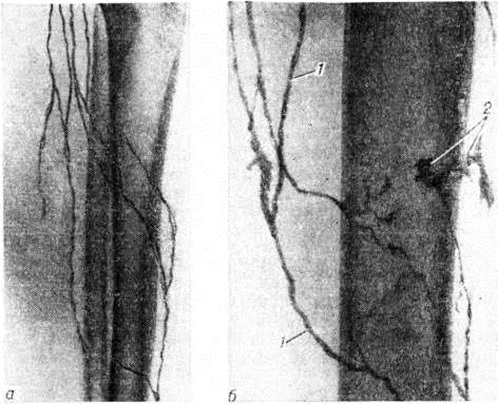

Особенностью лимфографии при поверхностной Лимфангиэктазия является возможность выполнять исследование путём чрескожной пункции расширенного лимфатических, сосуда. Вследствие повышенного лимфатических, давления контрастное вещество локализуется преимущественно в дистальных отделах поражённой области, выявляя расширенные лимфатических, сосуды и увеличенное их количество (рисунок).